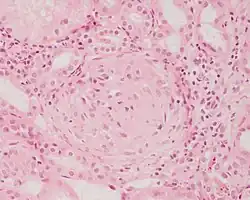

Photomicrograph of a kidney biopsy from a person with crescentic glomerulonephritis showing prominent fibrocellular crescent formation and moderate mesangial proliferation in a glomerulus. Hematoxylin and eosin stain.

Rapidly progressive glomerulonephritis

Crescentic glomerulonephritis induced by infective endocarditis on PAS staining and immunofluorescence. PAS staining (left) demonstrated circumferential and cellular crescent formation with interstitial nephritis. Immunofluorescence (right) demonstrated C3 positive staining in mesangial area.

Photomicrograph of renal biopsy showing crescent formation and tuft narrowing. Periodic acid silver methenamine stain.

Rapidly progressive glomerulonephritis, also known as crescentic GN, is characterised by a rapid, progressive deterioration in kidney function. People with rapidly progressive glomerulonephritis may present with a nephritic syndrome. In management, steroid therapy is sometimes used, although the prognosis remains poor.[9] Three main subtypes are recognised:[4]: 557–558

Histopathologically, the majority of glomeruli present "crescents". Formation of crescents is initiated by passage of fibrin into the Bowman space as a result of increased permeability of glomerular basement membrane. Fibrin stimulates the proliferation of endothelial cells of Bowman capsule, and an influx of monocytes. Rapid growing and fibrosis of crescents compresses the capillary loops and decreases the Bowman space, which leads to kidney failure within weeks or months.